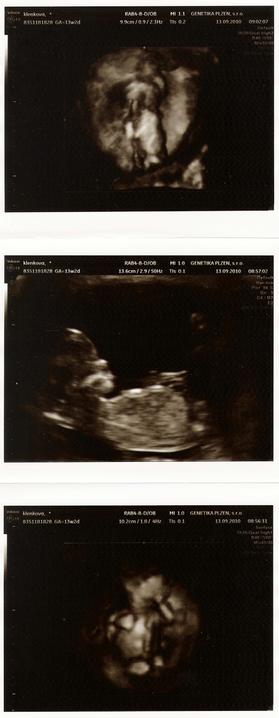

13.9.2010 jsme absolvovali screening v I. trimestru - pan doktor byl spokojený, NT=1,9 a nosní kůstku taky máme.